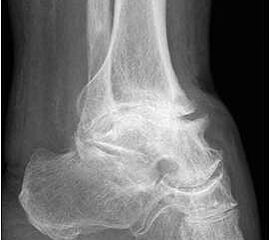

• Primäre oder posttraumatische Arthrose des OSG und USG (Abbildung 1, Abbildung 2).